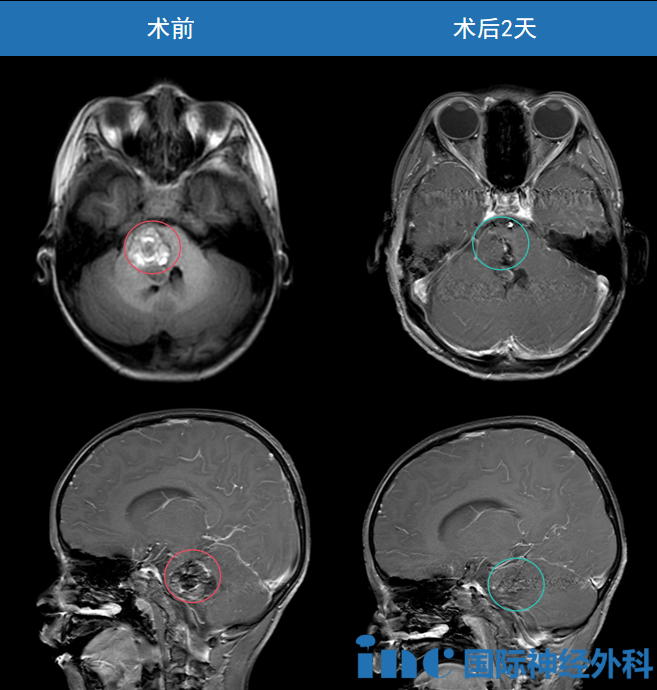

淼淼术前术后影像对比

紧急的MRI检查揭示了更令人担忧的事实:中脑及脑桥出现了新的病灶,最大层面已达34mmx29mm,海绵状血管瘤不仅未消,反而合并了出血。

最终,这颗盘踞在脑干的巨大海绵状血管瘤被成功全切,为淼淼清除了致命的威胁!